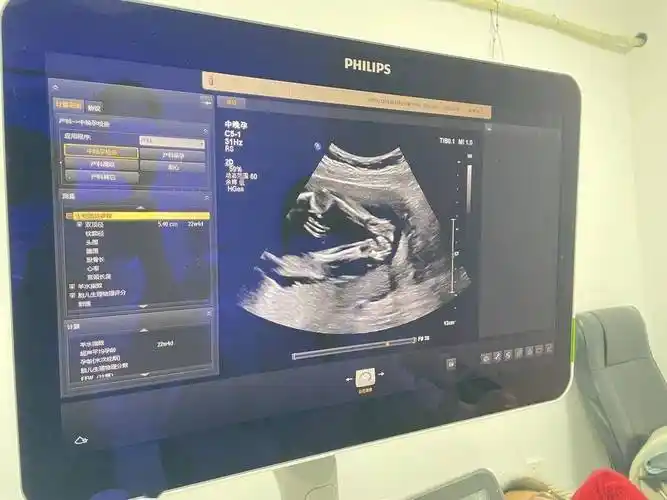

胡杏儿晒胎儿b超照 宝宝小脚丫超可爱(图)

准妈妈去体检,看到b超下的婴儿差点吓哭!

b超检查

孕5个月胎儿大排畸检查:这项检查通过b超检测技术完成,是整个孕育

而在b超单上出现的是字母q,将来很可能会生下女宝

产检时,若"b超单"上出现这5个字,腹中可能是位小王子